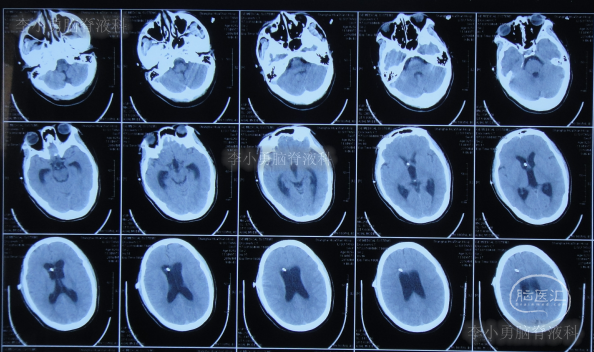

家属为进一步明确病因即2016年4月4日,第2次就诊并住入第二家的上海市静安区的某三甲医院,复查头颅影像后(图-3、图-4),给予按癫痫进行治疗。

图-3:2016年4月4日头颅CT

图-4:2016年4月4日头颅影像